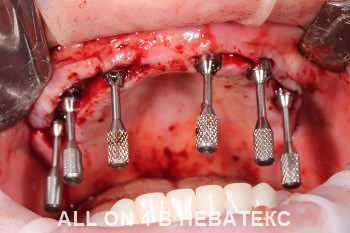

All-on-4 в клинике НЕВАТЕКС.МОСКВА

Во время операции